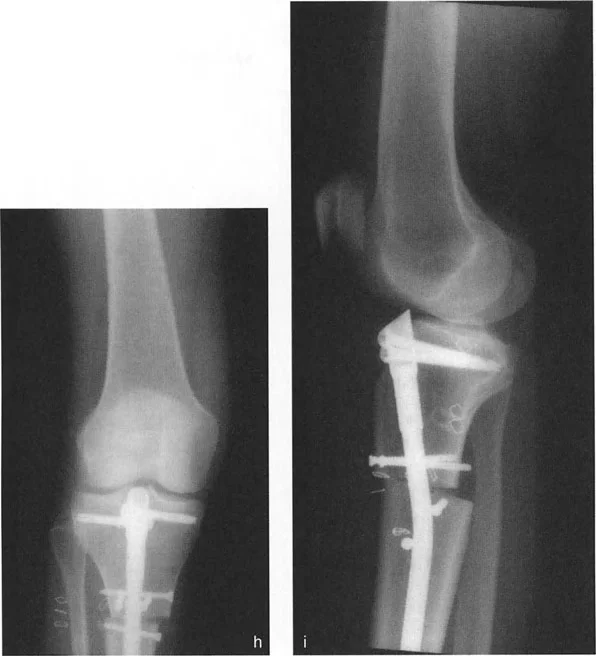

صورة بالأشعة السينية تظهر فشل التثبيت أحادي المسمار في الحفاظ على المحاذاة في المستوى السهمي

توفر الأشعة السينية أعلاه دليلاً سريريًا صارخًا لا يمكن إنكاره على هذا الفخ الميكانيكي الحيوي. تُظهر هذه الأشعة الأمامية والخلفية والجانبية قطع عظم قُببي بؤري في عظم الفخذ البعيد تم التعامل معه بمثبت أحادي الجانب غير كافٍ بمسمارين.

* الصورة f (منظر أمامي): بالنظر فقط إلى المستوى الأمامي، يبدو التصحيح جيدًا. يبدو المحور الميكانيكي متوازنًا، وقد يعتقد الجرّاح خطأً أن العملية كانت ناجحة.

* الصورة g (منظر جانبي): يتم الكشف فورًا عن النقص الكارثي في التحكم في المستوى السهمي. ينثني الجزء البعيد من عظم الفخذ بشكل كبير، مما يخلق تشوهًا شديدًا في التقوس الأمامي (Procurvatum). يعمل المسمار الوحيد في الجزء البعيد كنقطة ارتكاز، غير قادر تمامًا على مقاومة القوى المشوهة الهائلة للعضلات المحيطة. سيعاني هذا المريض من حركات ركبة متغيرة وعرج شديد.